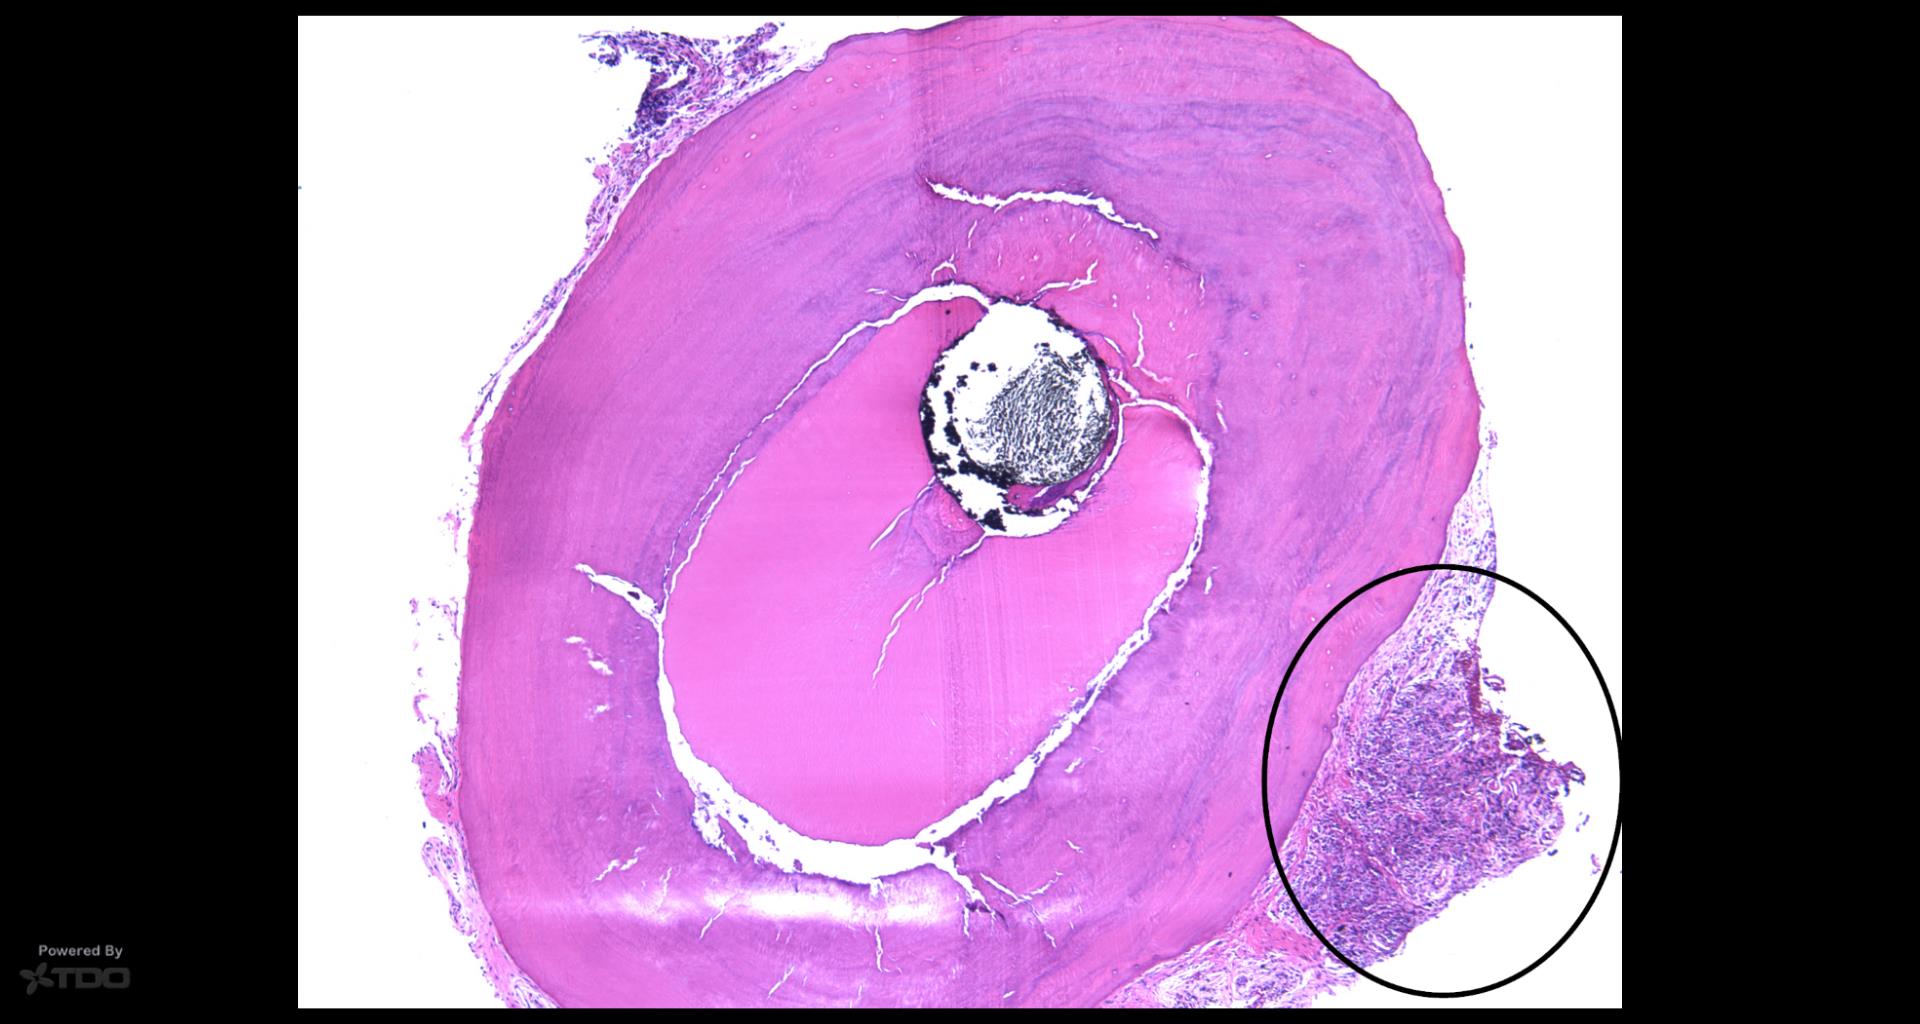

Older TDO’ers may remember this case that Rick sent me in 2012 from a surgery he did.. There was some bacterial morphotypes seen along the canal wall, but not very much. But on the outer root surface there was a lot of inflammation and a fungal stain suggests why…. gbc